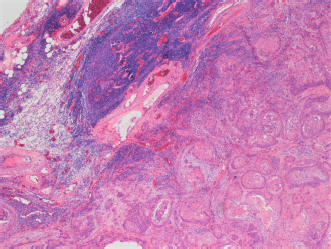

Fig. 3. Histopathological image of the biopsy from the cranial mediastinal mass showing neoplasia replacing normal thymic architecture. Necrotic areas not seen in this image.

Histopathological report on the cranial mediastinal mass established the diagnosis of squamous cell carcinoma. The neoplasm extensively replaced normal architecture (Fig. 3) and was associated with broad zones of necrosis. The squamous cells had pleomorphic features, including variation in cell and nuclear size and shape, as well as elevated mitotic activity. The mediastinal lymph node had reactive lymphoid elements without evidence of metastatic neoplasia.